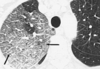

Consolidación alveolar

How well did you know this?

1

Not at all